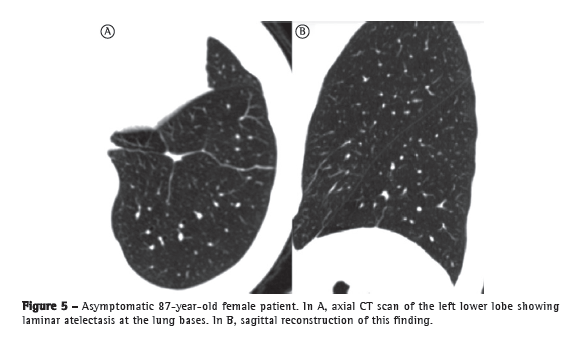

A CT scan of the lung parenchyma shows findings that are quite common in the elderly, and it is speculated that these findings are related to collagen changes. These findings are laminar atelectasis, mostly posterior and basal, located in the dependent regions of the lungs (Figure 5); subpleural linear thickening (Figure 6); areas of air trapping (Figure 7); bronchial thickening and ectasia (Figure 8); and lung cysts.(41,50-53)